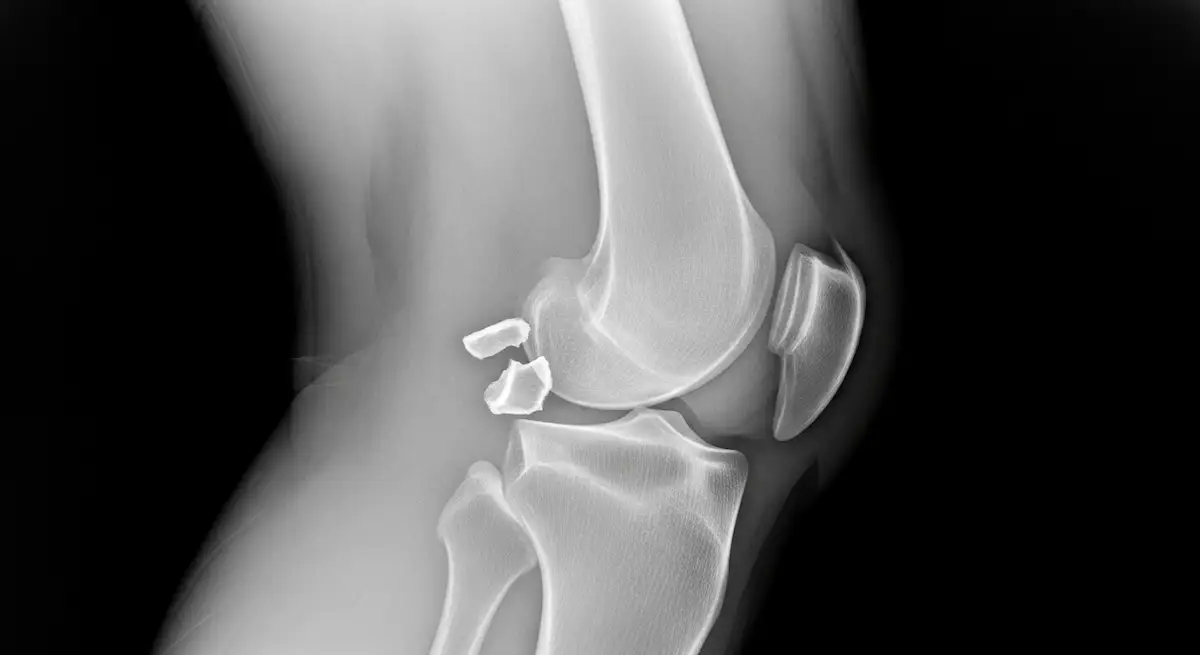

A fratura de Segond é uma pequena avulsão na margem lateral da tíbia, típica de entorses do joelho. Ela costuma vir acompanhada de lesão do ligamento cruzado anterior.

Trata-se de um fragmento ósseo arrancado onde as estruturas anterolaterais do joelho se inserem na tíbia lateral.

Apesar de pequena, a fratura de Segond sinaliza que houve força suficiente para afetar ligamentos e meniscos. Por isso, é considerada um marcador de instabilidade do joelho.

A fratura de Segond aparece com frequência em pacientes com lesão do LCA. O fragmento indica tração no complexo anterolateral, que ajuda a controlar a rotação da tíbia.

- A radiografia em AP costuma mostrar um pequeno fragmento elíptico junto ao planalto tibial lateral.